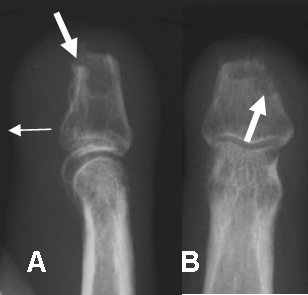

Fig 47 A. Osteomielitis PostQx.

A: Rx lateral y B: Rx AP. Amputación traumática de la falange media en el 3 dedo. Por persistencia del dolor se toma Rx encontrando gran edema de tejidos blandos (Flechas delgadas), irregularidad de los bordes óseos y área de osteolisis, por osteomielitis. (Flecha gruesa).